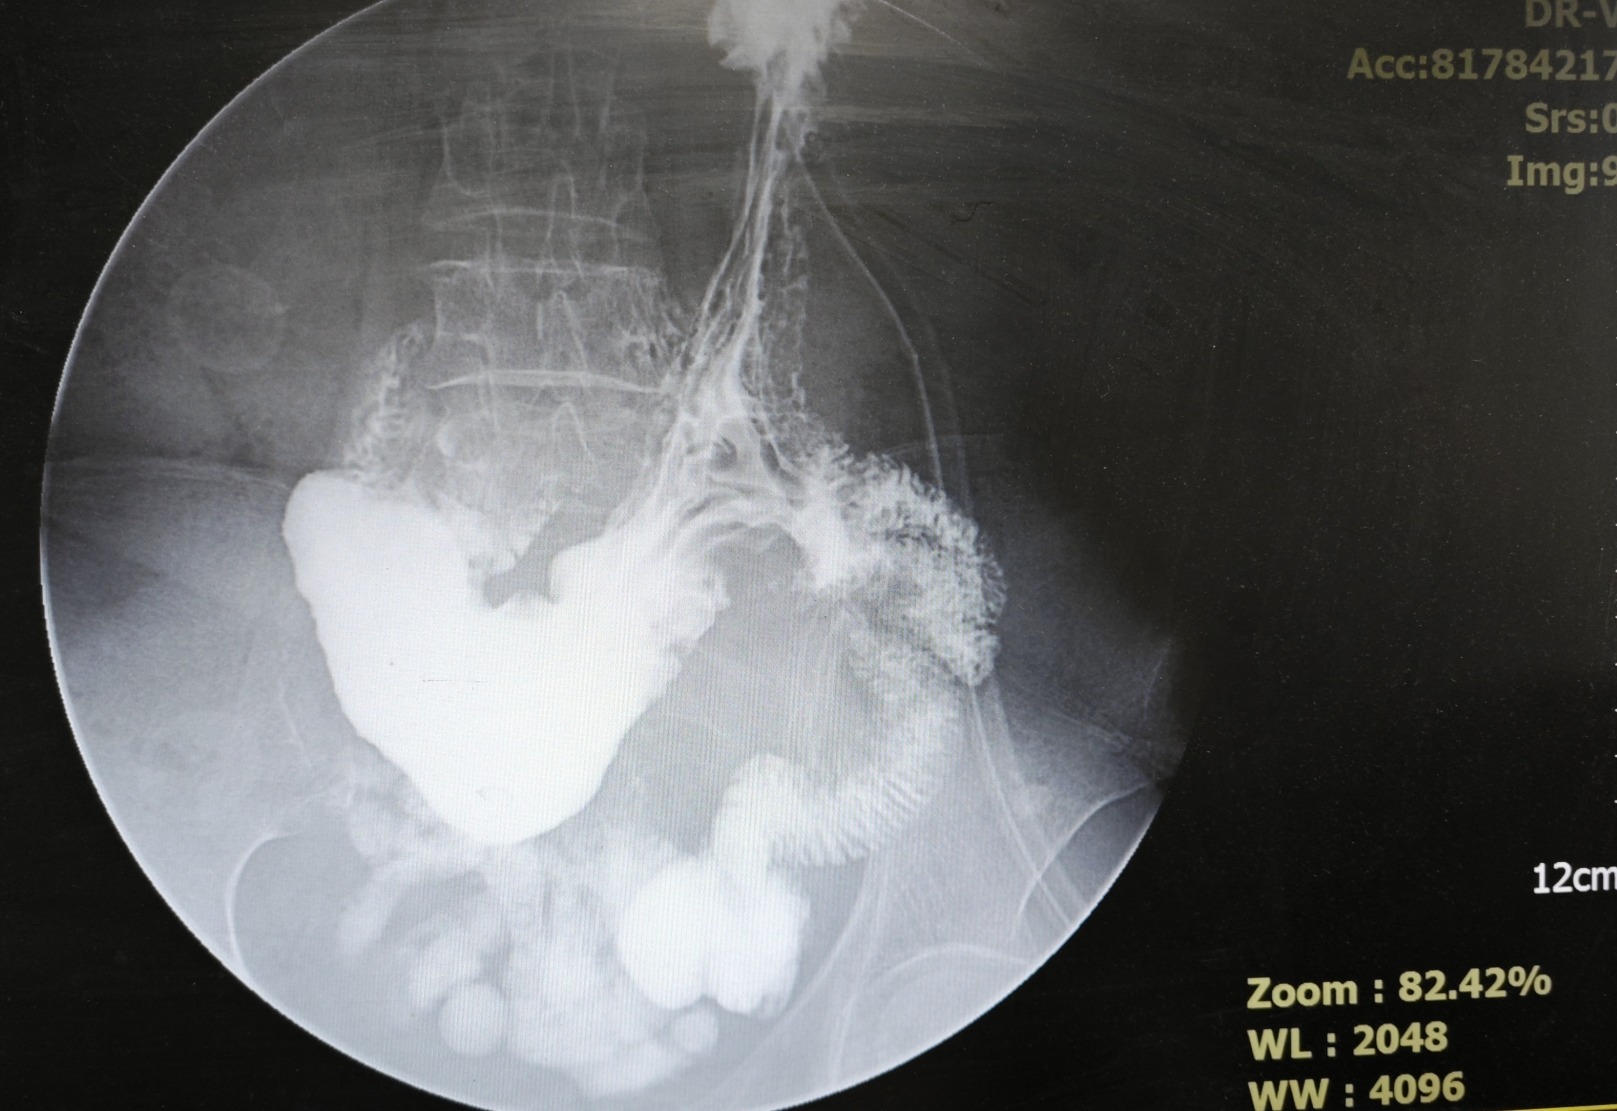

患者,女,68岁,久居黑龙江。饭后上腹胀痛5年,加重2年。自诉2年以来,午后无法进食。既往长期上腹疼痛病史。体重减轻15KG余,严重影响生活质量,BMI16.2。于当地辗转多家医院,胃镜提示十二指肠狭窄,幽门变形。均行保守治疗,无明显效果。闻名于我院就诊,在胃肠外科主任朱晋国主任医师带领下详细采集病史、体格检查并结合外院辅助检查组织科内术前讨论,考虑十二指肠狭窄因长期溃疡炎症所致,决定行全腹腔镜下胃空肠吻合术,选择最合适的Roux-en-y吻合术。制定周密的手术计划,并与家属进行了详细的沟通,患者家属非常信赖山东中医药大学第二附属医院,同意手术。

手术由主任医师朱晋国,副主任医师王东、主治医师秦凯强、张守康共同完成,患者术后顺利康复,术后第2天自主下床活动,术后第3天饮水逐渐过渡饮食,大大加快了术后的康复过程。